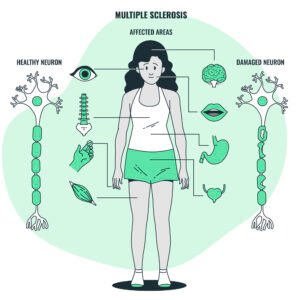

- Multiple Sclerosis